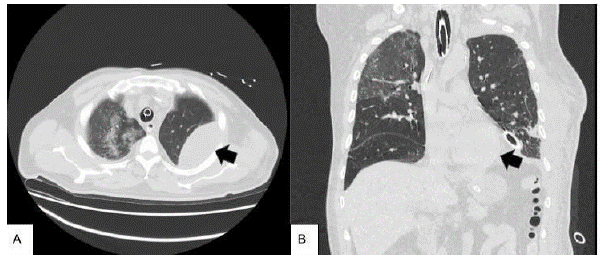

Al día 12 posoperatorio, presentó evolución clínica tórpida, con mala mecánica ventilatoria, requerimiento de intubación orotraqueal, elevación de reactantes de fase aguda y drenaje purulento por tubo a tórax por lo que se realizó nuevo estudio tomográfico que reportó hemotórax izquierdo y hematoma de pared torácica izquierda (Ver Figura 4), con necesidad de escalonamiento antibiótico a meropenem con continuación de linezolid y de reintervención para evaluar dehiscencia de sutura esofágica así como decorticación pulmonar por toracoscopia con pleurectomía parietal y lavado de cavidad.

Además se evidencia el compromiso pulmonar bilateral en patrón de vidrio esmerilado sugestivo de infección por COVID 19.

Figura 4 A. Flecha negra. Colección en pared lateral de hemitórax izquierdo 10x 5.4 x12.2 cm para volumen aproximado de 343 cc compatible con hematoma de pared torácica izquierda. B. Flecha negra. Hematoma previamente mencionado en una vista coronal.